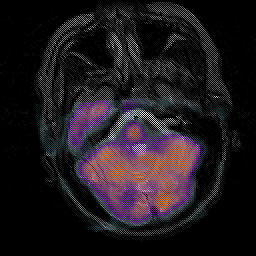

Subacute Stroke, overlay -- Slice #6

[Home][Help][Clinical] Slice 6